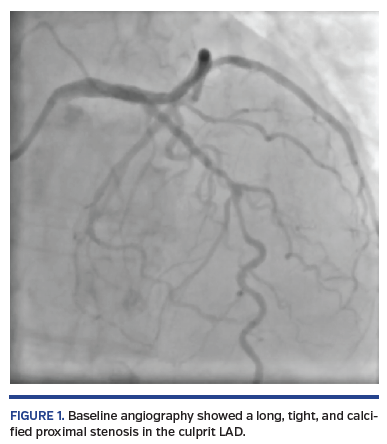

A short, 81-year-old woman presented with non-ST elevation acute myocardial infarction complicated with acute pulmonary edema. She was referred to urgent coronary angiography, performed via right distal transradial access, which is our default approach. The culprit left anterior descending (LAD) coronary artery was shown to have a long, tight, and calcified proximal-mid stenosis (Figure 1; Video 1), which was fixed by PCI with two drug-eluting stents (3 x 33 mm and 3.5 x 33 mm), requiring adequate pre- and postdilations with non-compliant balloons (2.5 x 20 mm and 3.5 x 20 mm, respectively). Surprisingly, the final angiogram showed an unexpected huge cavity spilling in-stent mid LAD perforation, with drainage to the left ventricle (Figure 2; Video 2). Promptly, the same postdilation NC 3.5 x 20 mm balloon was reinflated to 8 atm at the level of the CAP. After 10 minutes, there was some resolution. After a total 20 minutes of persistent balloon inflation without anticoagulation reversal, a final angiogram confirmed the CAP had been completely sealed without any residual contrast extravasation (Figure 3; Video 3). Transthoracic echocardiogram discharged pericardial effusion.